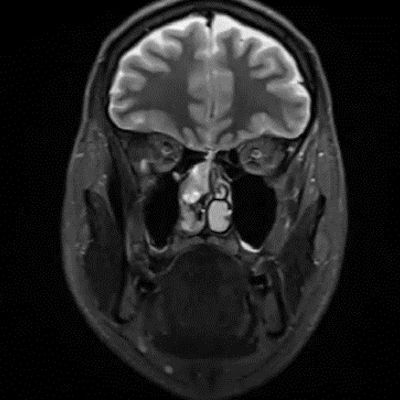

- A) Koronal T2A görntüde sağ süperior nazal kavite içerisinde hafif ekpansil karakterde, keskin sınırlı, nisbeten lobüle konturlu heterojen ara sinyal intensitye sahip yumşak doku lezyonu izleniyor (oklar).

- Estezionöroblastom görüntülemede tipik olarak nazal kavite tavanında, lamina cribrosa düzeyinden köken alan, etmoid sinüsler, orbita ve anterior kraniyal fossaya yayılım gösterebilen lobüle, agresif karakterli bir yumuşak doku kitlesi olarak izlenir ve sıklıkla komşu kemik yapılarda destrüksiyona neden olur. MR’da lezyon genellikle T1-ağırlıklı serilerde izo/hipointens, T2-ağırlıklı serilerde hiperintens sinyal özelliği gösterir ve kontrast sonrası heterojen güçlü kontrastlanma izlenir. İntrakraniyal uzanım varlığında tümör ile frontal lob parankimi arasında izlenen peritümöral periferik kistik değişiklikler, estezionöroblastom için literatürde tanımlanmış ayırt edici ve spesifik bir MR bulgusudur.

- Bununla birlikte görüntüleme bulguları her olguda tipik olmayabilir ve diğer sinonazal malignitelerle örtüşebilir. Bizim olgumuzda MR bulguları tipik özellikleri yansıtmamış olup, kesin tanı postoperatif histopatolojik inceleme ile estezionöroblastom olarak konulmuştur.